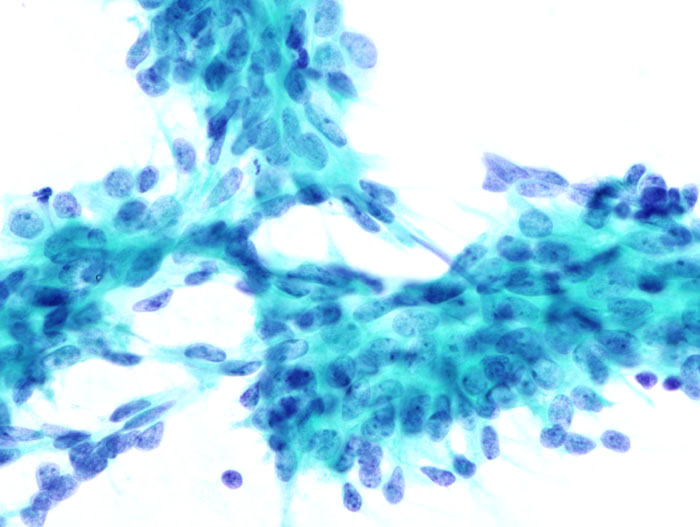

Intraductal papillomas are wart-like tumors that grow within the milk ducts of the breast.

Intraductal papillomas are benign.

Intraductal papillomas are distinguished by the presence of fibrovascular projections lined by epithelial (luminal) and myoepithelial cells.

In a premenopausal woman, intraductal papillomas typically manifest as bloody nipple discharge.

Intraductal papillomas must be distinguished from papillary carcinoma, which represents bloody nipple discharge.

On histology, papillary carcinoma has fibrovascular projections lined by epithelial cells but lacking underlying myoepithelial cells.

The risk of papillary carcinoma increases with age.